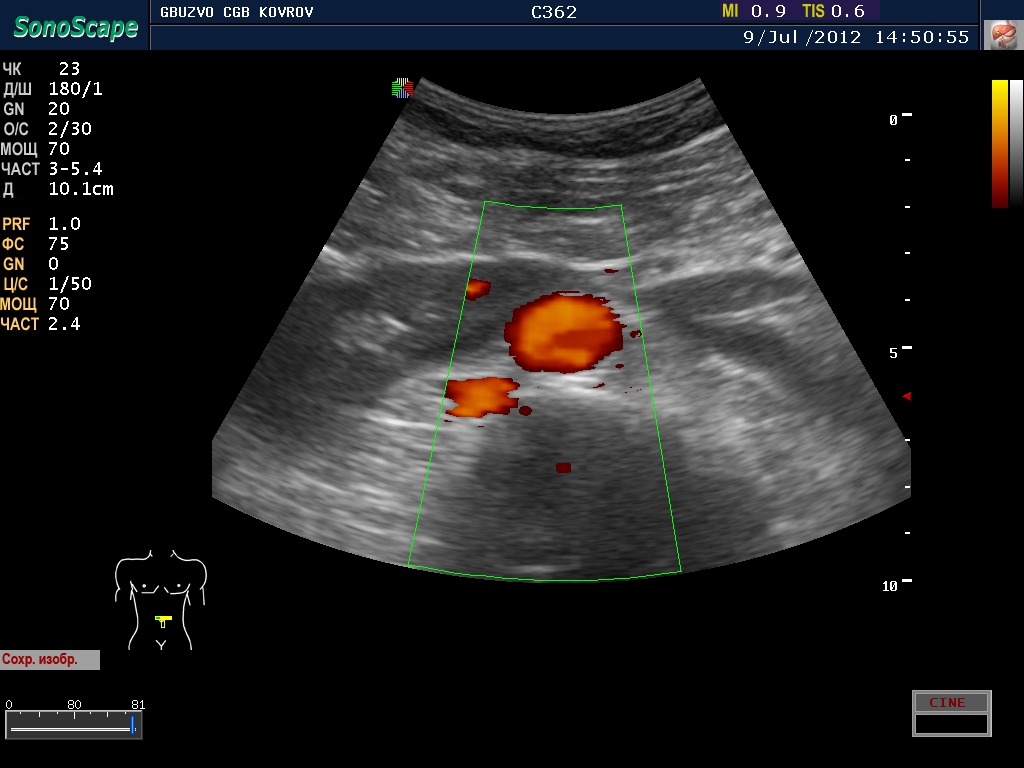

Добавлю с разрешения коллег, свое наблюдение...

Расположение. Сгрудились у аорты...

расположение аномальное - подковообразная почка 8-) четко виден перешеек!

В своё время не разъехались. А жить то ему это мешает? Наверное нет.

живет..хлеб жует...нет не мешает.